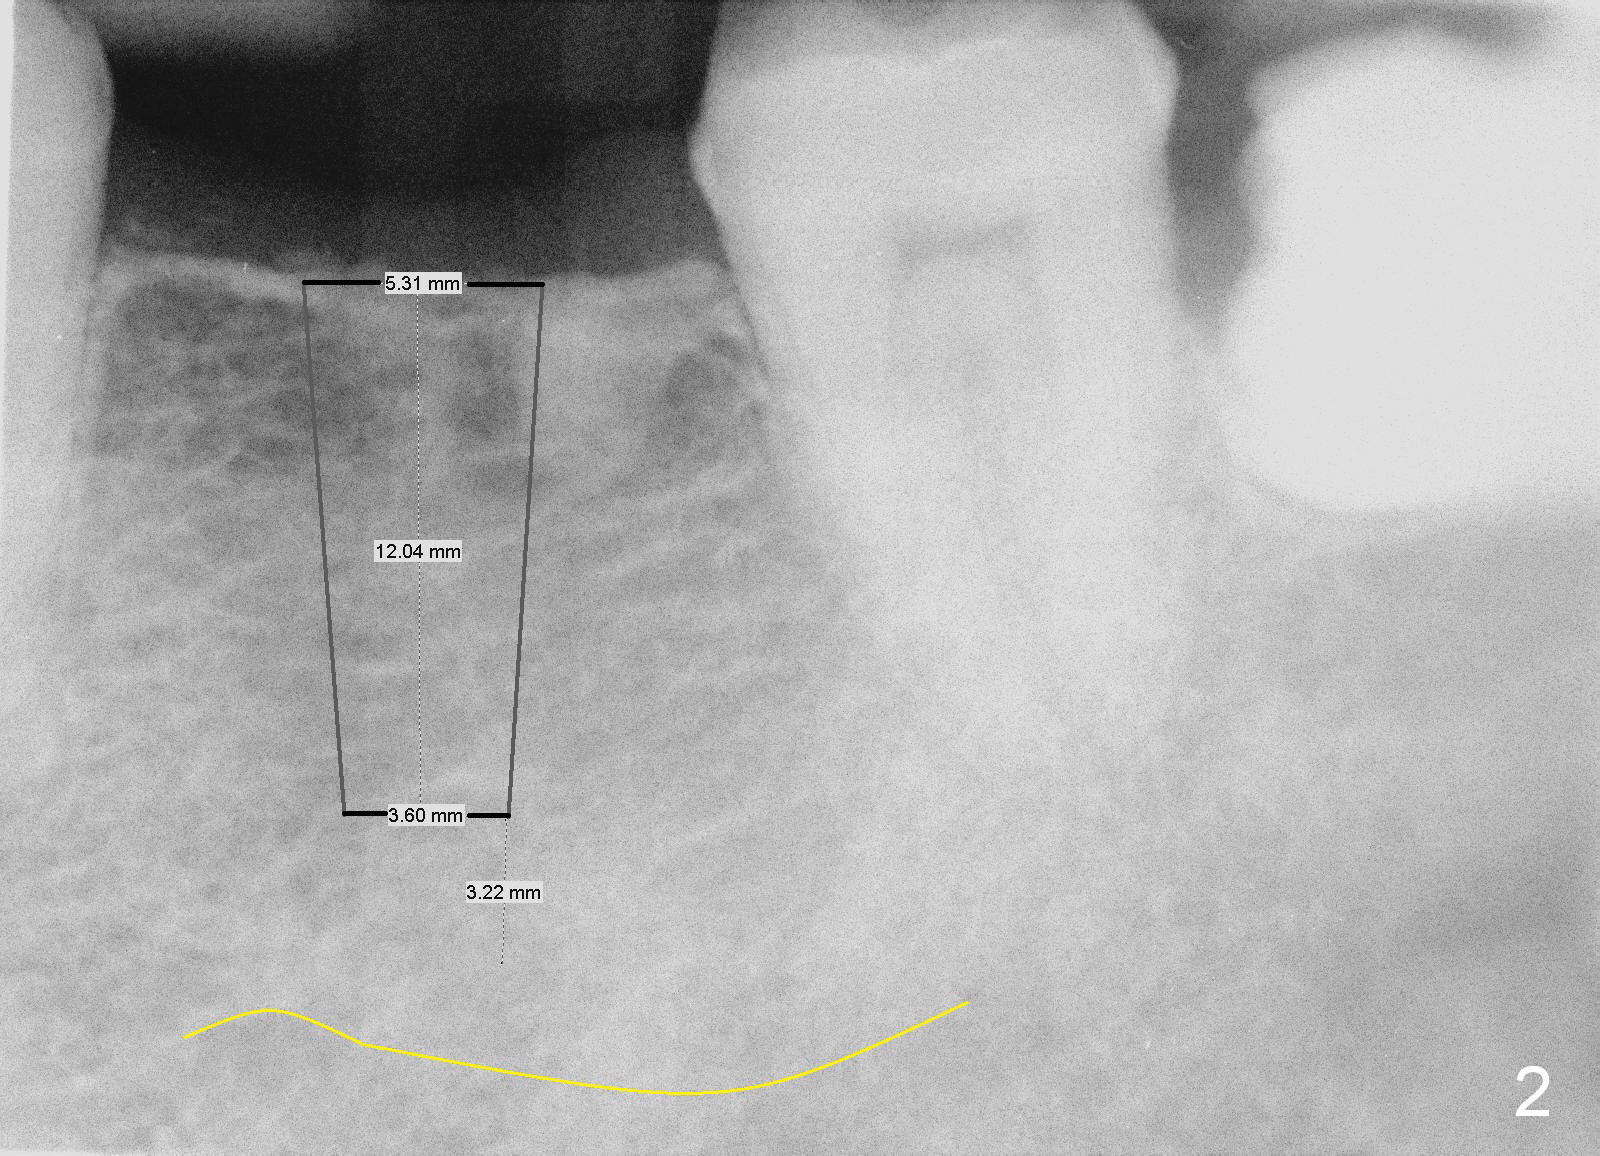

A 49-year-old man cannot quit smoking.  The lower left fixed partial prosthesis (FPD) has been dislodged (Fig.1).  It appears that the patient is a bruxer.  The bone height seems to be unlimited (yellow line in Fig.1,2: the upper border of the Inferior Alveolar Canal).  It should be safe to place a 12 or 14 mm long bone level implant (Fig.2).  The initial osteotomy depth is 12 mm.